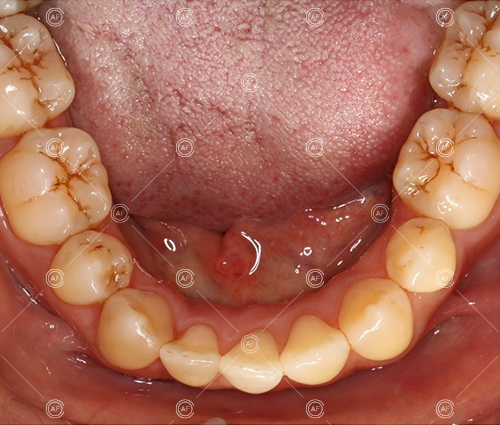

This patient (MH) began her active orthodontic treatment in October 2019 at almost 13 years old. She was unhappy with the appearance of her upper and lower teeth, and especially concerned about the unsightly nature of the high and buccally positioned upper left canine.

about this case…MH presented with class 1 incisors on the class 1 skeletal base with a slightly increased vertical proportion. She had severe crowding in the upper arch and moderate crowding in the lower. Due to the crowding in the lower arch, the lower centre line was off to the left by 2mm.